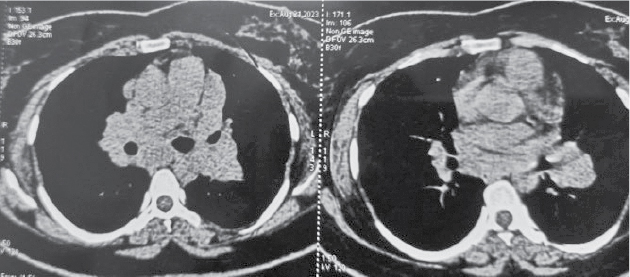

kidneys with mildly increased bilateral cortical echogenicity. Contrast-enhanced computed tomography (CECT) thorax was not feasible as creatinine was high, so noncontrast computed tomography (NCCT) thorax was done which showed multiple enlarged

mediastinal and hilar lymph nodes with minimal thickening of interlobular and intralobular septae in both lungs with areas of ground-glass opacities and diffuse centrilobular nodules(Figs. 1 and 2). Inter stitial lung disease work up sent,

Figure

2. NCCT Thorax - Mediastinal lymphadenopathy.